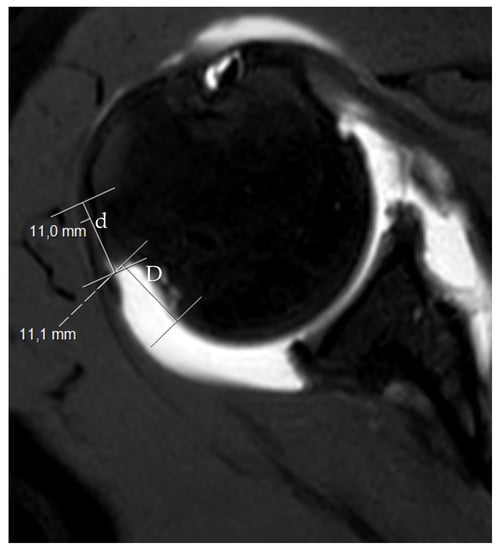

2. The Glenoid Track and Hill–Sachs Lesions: On-Track and Off-Track